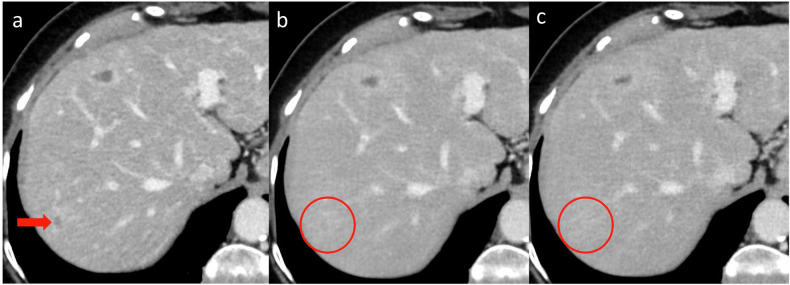

Objectives: Deep learning reconstruction (DLR) has shown promising image denoising ability, but its radiation dose reduction potential remains unknown. The objective of this study was to investigate the diagnostic performance of DLR compared to iterative reconstruction (IR) in the detection of liver lesions at standard-dose and reduced-dose CT.

Materials and methods: Participants with known liver metastases from gastrointestinal and pancreatic adenocarcinoma were prospectively included from routine follow-up (October 2020 to March 2022). Participants received standard-dose CT and two additional reduced-dose scans during the same contrast administration, each reconstructed with IR and high-strength DLR. Two radiologists evaluated images for the presence of liver lesions, and a third established a reference standard. Diagnostic performance was compared using McNemar's test and mixed effects logistic regression.

Results: Forty-four participants (mean age 66 years ± 11 [standard deviation], 28 men) were evaluated with 348 included liver lesions ≤ 20 mm (297 metastases, 51 benign; mean size 9.1 ± 4.3 mm). Mean volume CT dose index was 14.2, 7.8 mGy, and 5.1 mGy. Between algorithms, no significant difference in lesion detection was observed within dose levels. Detection of 233 lesions ≤ 10 mm was deteriorated with lower dose levels despite DLR denoising, with 185 detected at standard-dose IR (79.4%; 95% CI: 73.5-84.3) vs 128 at medium-dose DLR (54.9%; 95% CI: 48.3-61.4; p < 0.001) and 105 at low-dose DLR (45.1%; 95% CI: 38.6-51.7; p < 0.001).

Conclusion: Diagnostic performance for liver lesion detection was comparable between algorithms. When the detection of smaller lesions is important, DLR did not facilitate substantial dose reduction.

Key points: Question Methods to reduce CT radiation dose are desirable in clinical practice, and DLR has shown promising image denoising capabilities. Findings Liver lesion detection was comparable for DLR and IR across dose levels, but detection of smaller lesions deteriorated with lower dose levels. Clinical relevance Although potent in image noise reduction, the diagnostic performance of DLR is comparable to IR at standard-dose and reduced-dose CT. Care must be taken in pursuit of dose reduction when the detection and characterization of smaller liver lesions are of clinical importance.